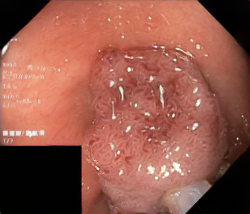

A few sample images and the corresponding masks of the polyp dataset in HyperKvasir are shown in Fig 2. The polyp images are RGB images. The masks of the polyp images are single-channel images with white () for true pixels, which represent polyp regions, and black () for false pixels, which represent clean colon or background regions. In this dataset, there are different sizes of polyps. The distribution of polyp sizes as a percentage of the full image size is presented in the histogram plot in Fig 3, and we can observe that there are more relatively small polyps compared to larger polyps. Additionally, a subset of this dataset was used to prove that the performance of segmentation models trained with small datasets can be improved using our SinGAN-Seg pipeline, and the whole dataset was used to show the effect of using SinGAN-Seg generated synthetic images instead of a large dataset which has enough data to train segmentation models. In this regard, this dataset was used for two purposes:

After training SinGAN-Seg models, we generated random samples per real image using the input scale , which is the lowest scale that uses a random noise input instead of a re-scaled input image. For more details about these scaling numbers and corresponding output behaviors, please refer to the vanilla SinGAN paper [56]. Three randomly selected training images and the corresponding first synthetic images generated using scale are depicted in Fig 4. The first column of the figure represents the real images and the ground truth mask annotated from experts. The rest of the columns represent randomly generated synthetic images and the corresponding generated mask.